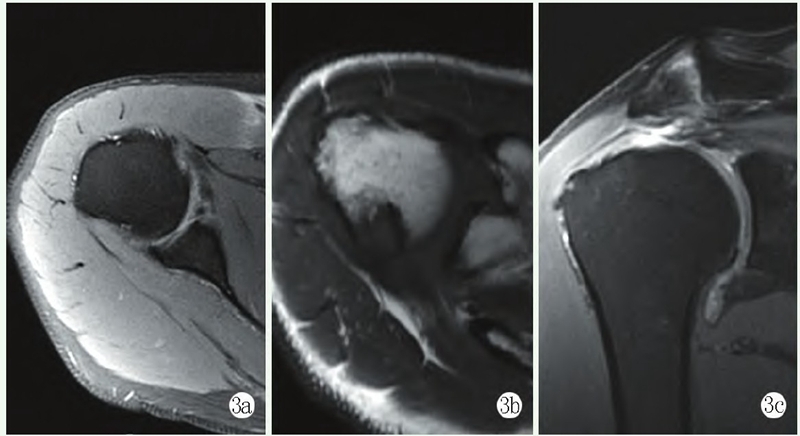

手术:采用全麻联合臂丛神经阻滞麻醉。取左侧卧右肩外展牵引下关节镜体手术位。建立右肩后方及前方标准关节镜入路探查盂肱关节。镜下见肱骨头内旋脱位,前下盂唇撕裂,冈上肌撕裂并回缩,肩胛下肌撕裂,肱二头肌长头腱完好。肩峰下入路探查,见冈上肌全层撕裂并回缩(图3d)。探查盂肱关节肱骨头后方见Hill-Sachs损伤(图3e),涉及大部分关节面,容易发生脱位。术中行肩峰成形术后,在冈上肌足印区置入带线锚钉2枚,将锚钉尾端缝线穿过冈上肌组织后打结修复,再用2枚外排钉加强固定,在肱骨小结节置入带线锚钉2枚,将锚钉尾端缝线穿过肩胛下肌组织后打结修复。松解前下盂唇撕裂组织,在肩盂6点、4点处分别置入带线锚钉,用缝合钩将锚钉尾部缝线穿过盂唇组织缝合固定,肱骨Hill-Sachs骨缺损区置入带线锚钉2枚,将锚钉尾端缝线穿过冈下肌组织后打结填塞固定,修复后活动肩关节无受限、无脱位。

图3d: 术中镜下见撕裂的肩袖;3e: 镜下见巨大Hill-Sachs损伤,涉及大部分关节面